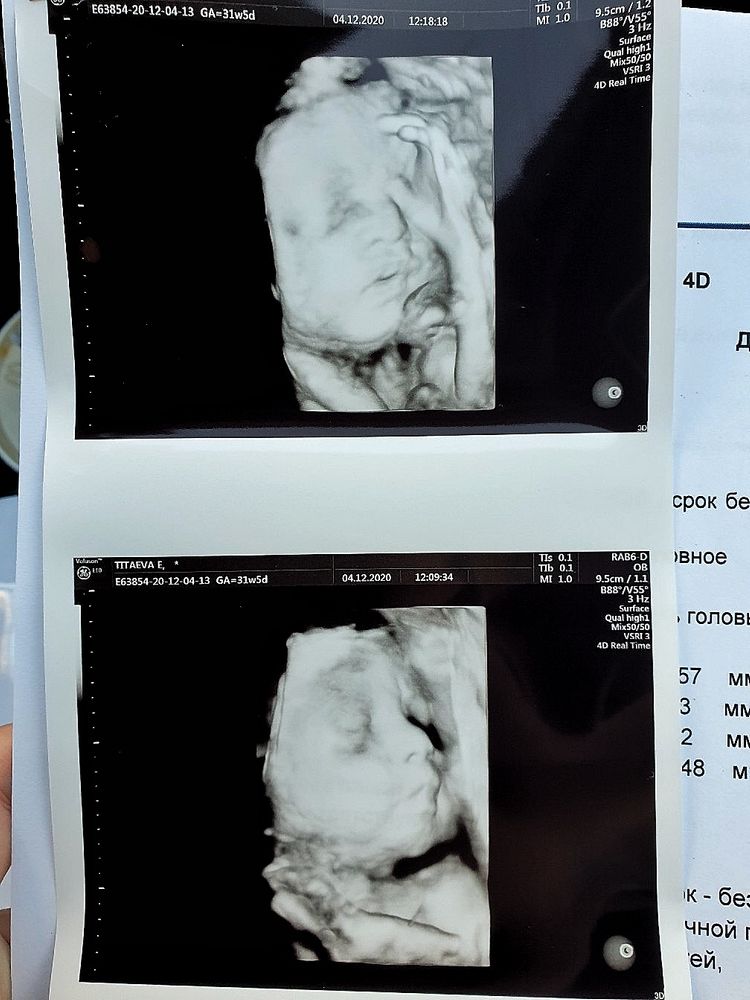

Лучше всего личико видно, когда ещё много околоплодных вод, 21-23 недели должно быть ещё норм. Я не помню, на каком сроке прошлый раз была, но вот в 31 неделю уже толком не посмотришь, т.к. тесновато, у него то ручки перед лицом, то пуповина, то в матку упёрся мордашкой

Почти 31 неделька и 21 неделька